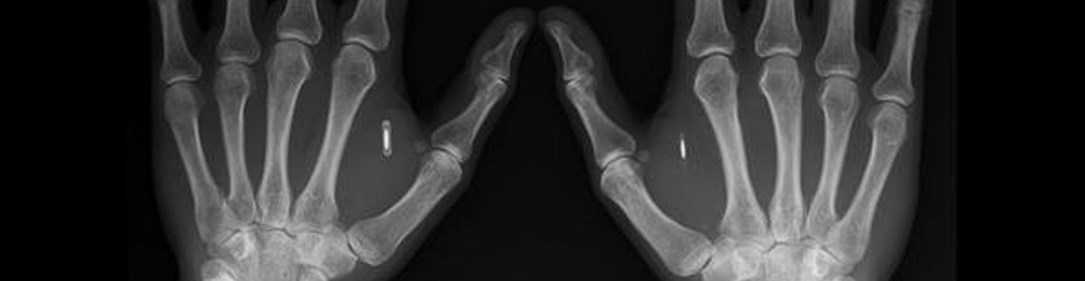

Soyons sérieux, certains parlent de flicage, de non-respect de la vie privée et autre déblatération mais il s’agit tout simplement d’une méthode de remplacement d’un badge de société que tout le monde perd un jour ou oublie dans son véhicule, voire échangé avec un collègue pour qu’il pointe à votre place. De plus, ces employés étaient volontaires et cette puce, implantée dans la chair entre le pouce et l’index par un tatoueur, est aussi utilisée comme identifiant sur leur ordinateur de travail.

Quelques informations sont aussi sauvegardées sur la puce afin de pouvoir échanger une espèce de carte de visite virtuelle, mais je ne vois pas très bien où est le mal… étant donné que cette démarche est tout à fait volontaire. Cette puce peut ensuite être désactivée à tout moment, comme un badge. Bon, d’accord avec vous, il vous faudra repasser par la case torture si vous quittez la boite mais, à l’avenir, pourquoi ne pas imaginer une puce générique qui serait valable partout dans le monde pour accéder aux bâtiments ou aux aéroports ? Elle pourrait contenir vos billets d’avion ou vos places de cinéma, réservées depuis Internet.